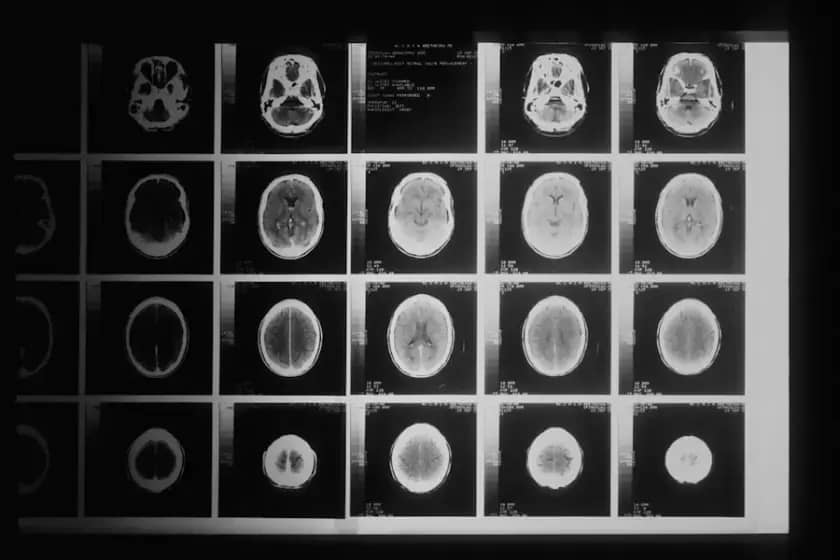

Dijagnoza, lečenje i recidiv

Dijagnoza se potvrđuje CT-om ili magnetnom rezonancom. Lečenje meningioma uključuje posmatranje, operaciju, radioterapiju, radiohirurgiju i ponekad hemoterapiju. Detaljna molekularna analiza može pomoći u izboru terapije. Meningiom može da se vrati nakon lečenja, pa je potrebno dugotrajno praćenje pacijenata. Petogodišnja stopa preživljavanja za meningiome II i III stepena iznosi 63,5 odsto.